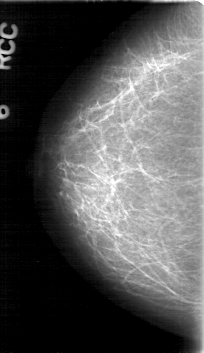

D_4083_1.RIGHT_CC

RIGHT_CC LINES 5281 PIXELS_PER_LINE 3046 BITS_PER_PIXEL 12 RESOLUTION 43.5 NON_OVERLAY

FILE: D_4083_1.LEFT_CC.OVERLAY

TOTAL_ABNORMALITIES 1

ABNORMALITY 1

LESION_TYPE MASS SHAPE OVAL MARGINS OBSCURED

ASSESSMENT 0

SUBTLETY 5

PATHOLOGY BENIGN

TOTAL_OUTLINES 1

BOUNDARY